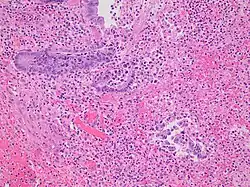

Even for clinically certain appendicitis, routine histopathology examination of appendectomy specimens is of value for identifying unsuspected pathologies requiring further postoperative management.[75] No sign of appendicitis in specimens, negative appendectomy, varies but has been estimated to occur in 13% of specimens.[76] Notably, appendix cancer is found incidentally in about 1% of appendectomy specimens.[77][78]

Pathology diagnosis of appendicitis can be made by detecting a neutrophilic infiltrate of the muscularis propria.

Periappendicitis (inflammation of tissues around the appendix) is often found in conjunction with other abdominal pathology.[79]

-

Micrograph of appendicitis and periappendicitis. H&E stain. -

Micrograph of appendicitis showing neutrophils in the muscularis propria. H&E stain. -

Acute suppurative appendicitis with perforation (at right). H&E stain.